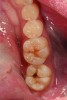

A 48-year-old patient presented with an old, failing Class I alloy restoration and showed recurrent decay on the lower molars (Figure 9). After the existing alloy was removed, the remaining tooth structure was evaluated. It was determined that despite the significant extent of caries present, it would be possible to perform a minimally invasive procedure using an injectable composite resin and an RMGI (Figure 10).

After removing the infected dentinal layer, a caries-detection stain was used to determine if further tooth removal would be necessary. On removal of all infected dentin, a chlorhexidine gluconate swab (CAVITY CLEANSER™ 2% Chlorhexidine Digluconate, BISCO, Inc.) was used to remove any surface bacteria on the prepared site. Next, a polyacrylic acid scrub was performed for 20 seconds to condition the dentin surface. An RMGI (GC Fuji II LC) was sculpted and light-cured to cover the affected and unaffected dentin.4,13,18,19 After the RMGI liner was fully cured, a micropreparation diamond bur (830RM.FG.009, Komet USA) was used to refine the internal form of the preparation. Marginal beveling to a 45° taper was completed along the cavosurface of the final tooth preparations.15